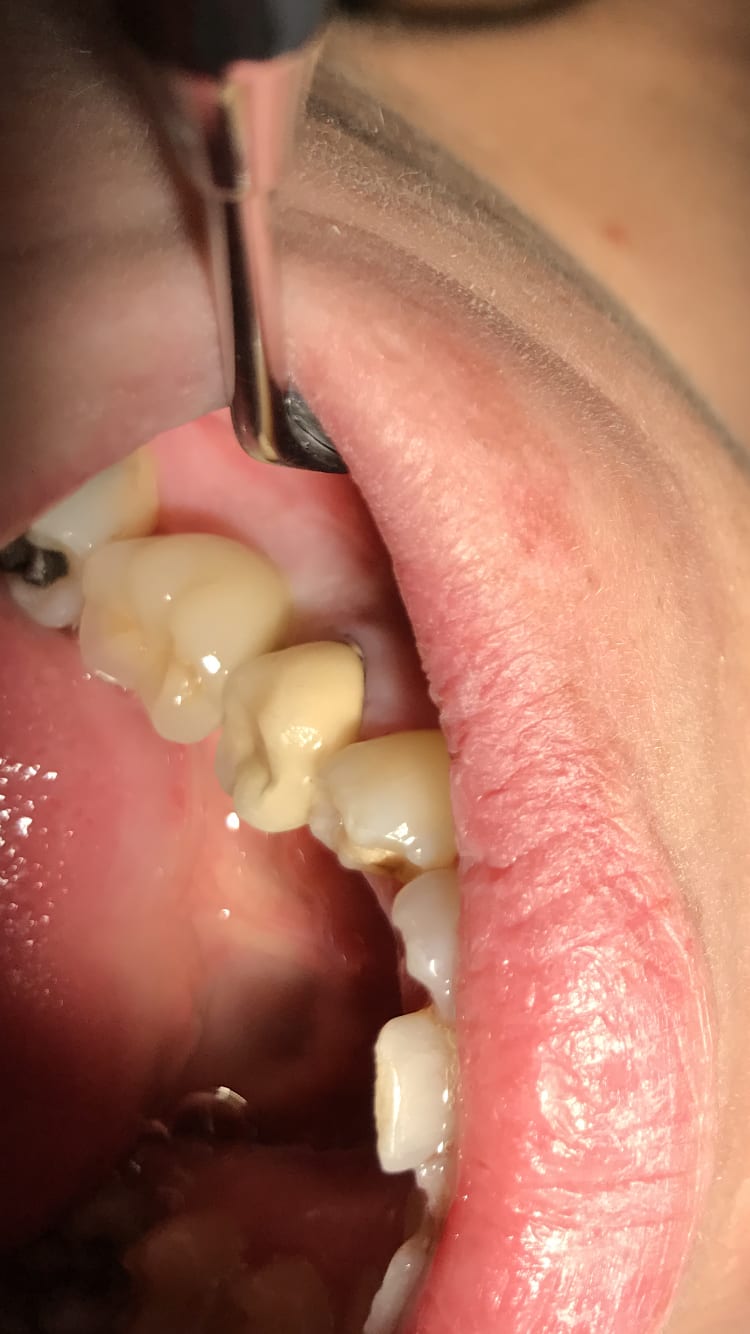

Ça vieillit toujours aussi bien les composites.

131a1fd8 dccc 4057 a3f8 6e1ca79ff413 t1km2e - Eugenol